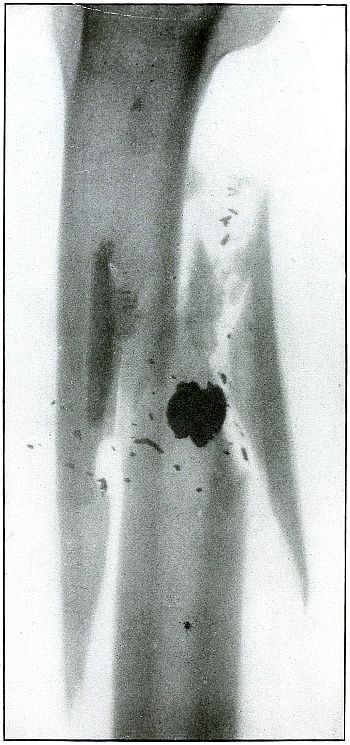

| 59. |

Gunshot wound, knee |

128 |

| 60. |

Gunshot fracture, tibia and fibula |